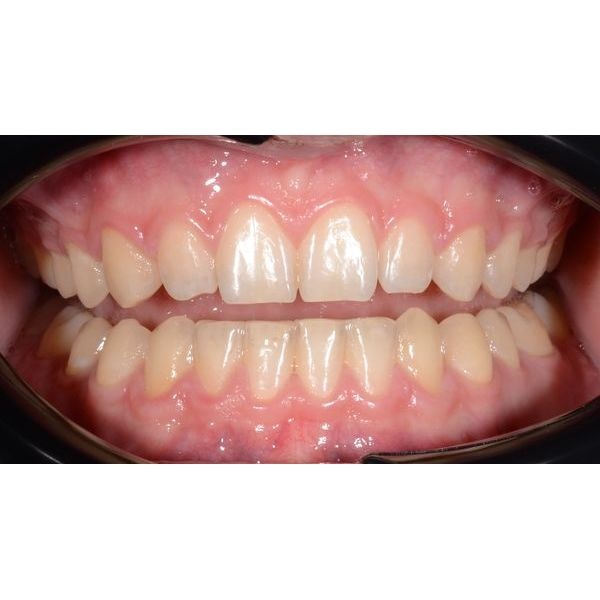

В итоге лечение прошло без осложнений и в короткие сроки. Оно длилось 1 год 6 месяцев. За это время мужчине изменили глубину перекрытия зубов в переднем отделе, закрыли промежутки на верхней челюсти, создали плотные межзубные контакты в боковых отделах и исправили скученность зубов — достигли стабильной функциональной и эстетической окклюзии (плотного и правильного смыкания зубов).

Чтобы сохранить результат, пациенту установили несъёмные ретейнеры (проволочные конструкции, удерживающие зубы в нужном положении) и изготовили индивидуальную ретенционную капу на верхнюю челюсть. Мужчину проинструктировали по поводу режима ношения и уходу за ретенционными аппаратами.

Во взрослом возрасте довольно сложно решиться на исправление прикуса, но клинический случай показывает, что это возможно, и правильное положение зубов нужно не только для эстетики, но и для сохранения зубов и их функциональных возможностей.